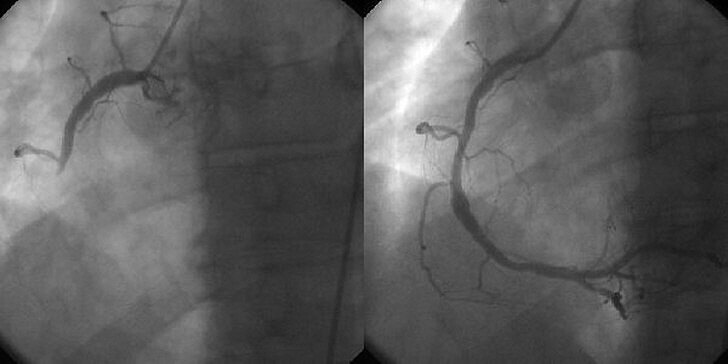

경피적관상동맥중재술은 심장의 관상동맥 협착을 치료하는 수술입니다. PCI는 관상동맥조영술(Coronary angiography)을 시행하면서 경피적관상동맥성형술(PTCA, percutaneous transluminal coronary angioplasty)을 시술하고 관상동맥이 좁아진 부위에 스텐트(stent)를 삽입하는 것을 포함합니다.

대퇴동맥(femoral artery) 또는 요골동맥(radial artery)을 통해 혈류에 접근한 후 관상동맥카테터를 사용하여 관상동맥에 풍선을 삽입해서 좁아진 관상동맥의 내경을 넓히고 관상동맥이 넓어진 상태를 유지할 수 있도록 스텐트를 삽입합니다.